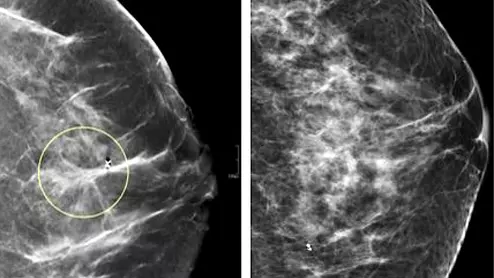

Comparison of a 2D digital mammogram and breast tomosynthesis 3D mammography from UCSF.

Since being approved by the U.S. Food and Drug Administration in 2011, DBT has become the most common method for breast cancer screening, and as of September 2022, 84% of all U.S. mammography screening facilities housed DBT units.